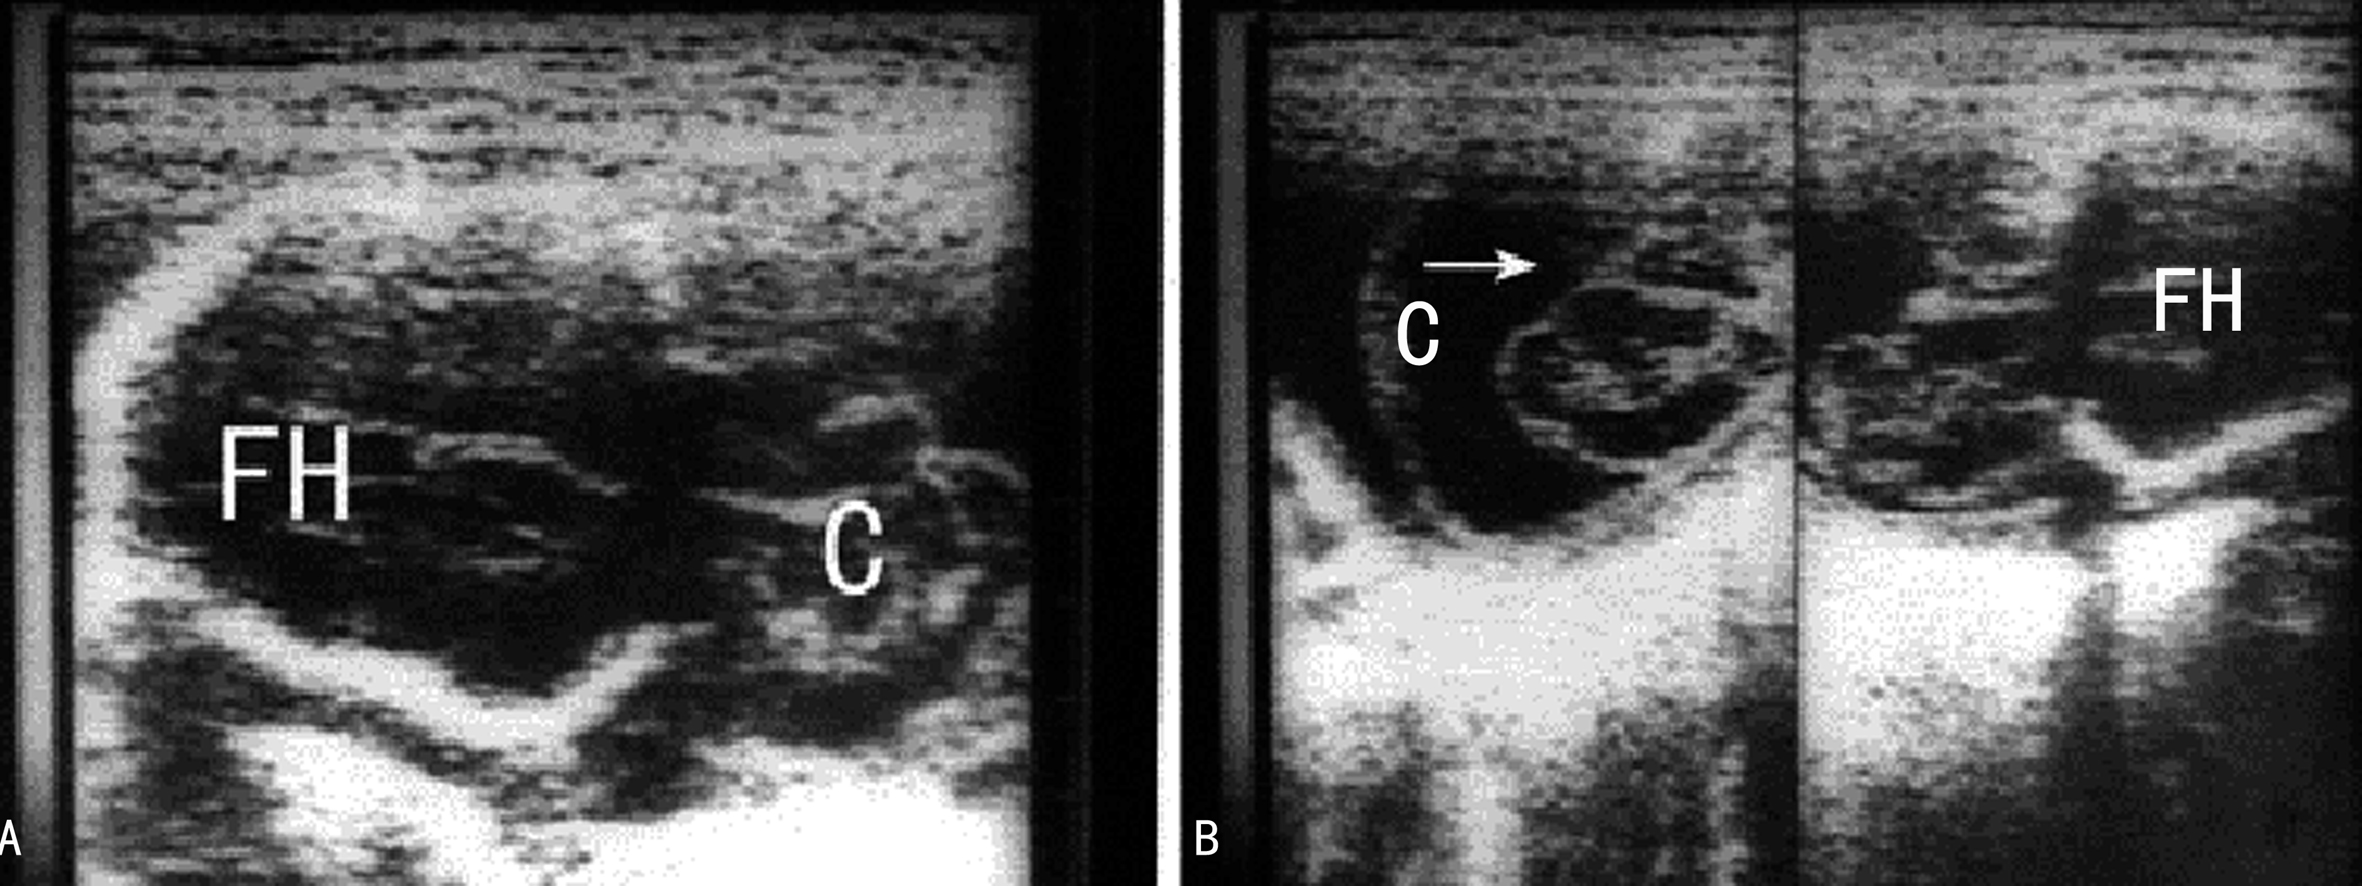

早孕期头颅小或者颅骨形态不规则,在头部轮廓外可显示包块样回声;随着胎儿的生长图像显示的愈加典型。经阴道超声可以看到早孕晚期的颅骨缺损处。胎儿颅骨显示后可以在颅骨外显示包块回声,局部颅骨显示缺损(图1),通过相互垂直的两个断面测量颅骨缺损的大小可以评估缺损的面积及突出物的大小(图2,图3)。有些小的缺损不能显示,仅能看到颅骨旁突出去的小囊样结构。突出的回声内部由于疝出的组织不同而有不同的表现,呈囊性或者囊实性混合回声(图1),“囊套囊”或者“靶环征”提示第四脑室脱垂,突出至颅底及眼部的脑膜膨出常难以于产前做出诊断。70%~80%伴有脑室扩张(图1A),25%伴小头畸形。除脑部异常回声外,其他部位检查可以发现伴发的畸形。

图3 AB示胎儿巨大脑膜脑膨出(C)